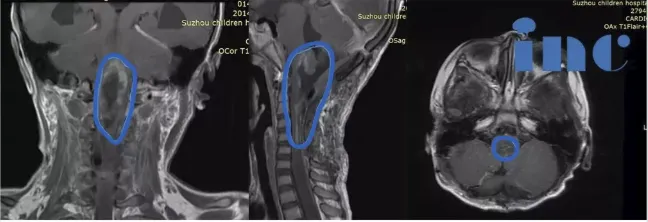

术前MR影像

由于琦琦的脑肿瘤偏大,且病变范围广,位于脑干延髓,一直延伸至颈5节段脊髓,这是人的呼吸、循环、颅神经、肢体功能等众多神经核团及传导束所在部位,因此,想要尽可能全切肿瘤并保护众多神经核团及传导束的难度较大,可能面临脑干水肿、呼吸功能障碍、后组脑神经功能障碍、脑积水等风险,严重者有意识障碍、肢体瘫痪等并发症。